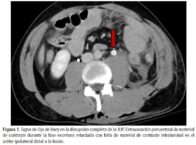

La extravasación de orina recubriendo la pared ureteral, con falta de material de contraste intraluminal creó una apariencia de ojo de buey en la fase tardía de la tomografía computarizada (fig.1).

La falta de material de contraste en la luz ureteral con extravasación del contraste alrededor del uréter en el lado lesionado crea el signo del ojo de buey en la tomografía computarizada. Este hallazgo radiológico es muy sugestivo de una rotura completa de la JUP y justifica una evaluación adicional con imágenes retrógradas para un diagnóstico temprano.

La extravasación urinaria periureteral con falta de contraste intraluminal en el uréter ipsilateral distal puede verse como el signo del ojo de buey en la fase excretora de una tomografía computarizada. Este hallazgo puede ayudar en la identificación temprana de la disrupción completa de la JUP y debería generar la obtención de imágenes de ureteropielografía retrógrada para una evaluación adicional y una posible intervención temprana.